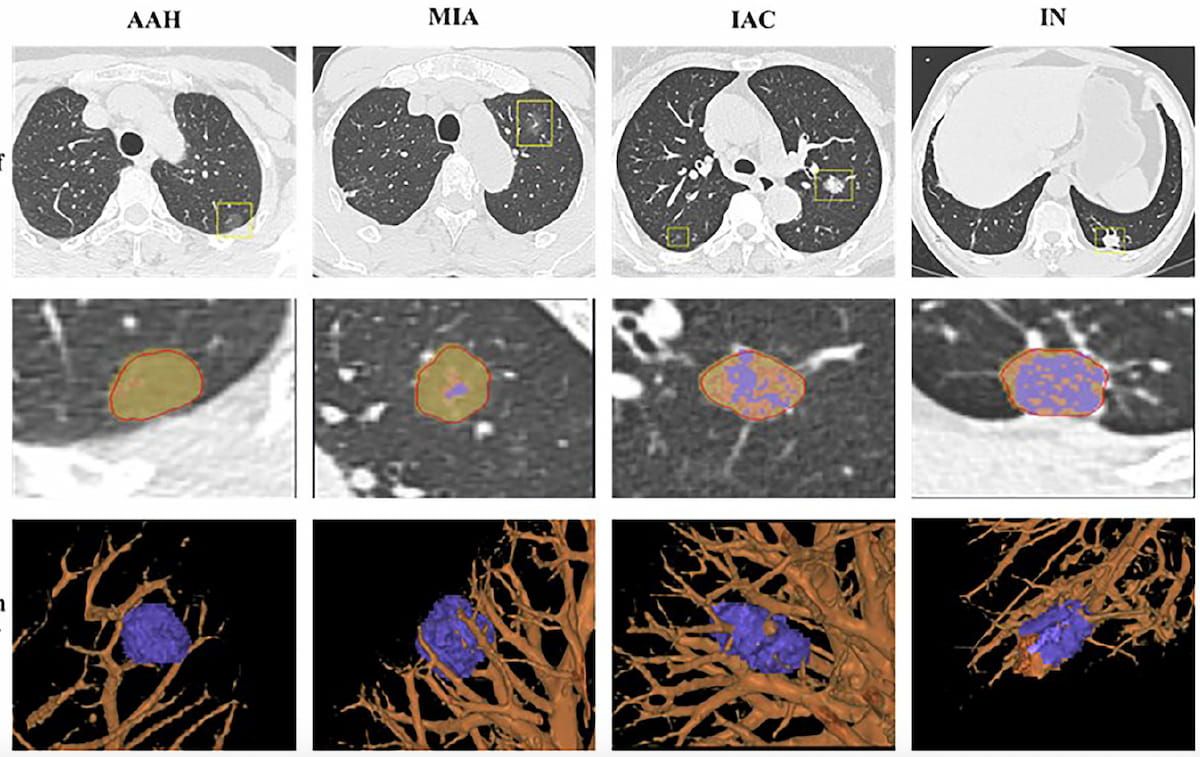

Emerging research shows that a multiple time-series deep learning model assessment of CT images provides 20 percent higher sensitivity than a delta radiomic model and 56 percent higher sensitivity than a clinical model for prognostic evaluation of ground-glass nodules.